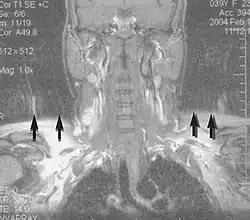

Musculoskeletal

Applications in the musculoskeletal system include spinal imaging, assessment of joint disease, and soft tissue tumors.[32] Also, MRI techniques can be used for diagnostic imaging of systemic muscle diseases including genetic muscle diseases.[33][34]